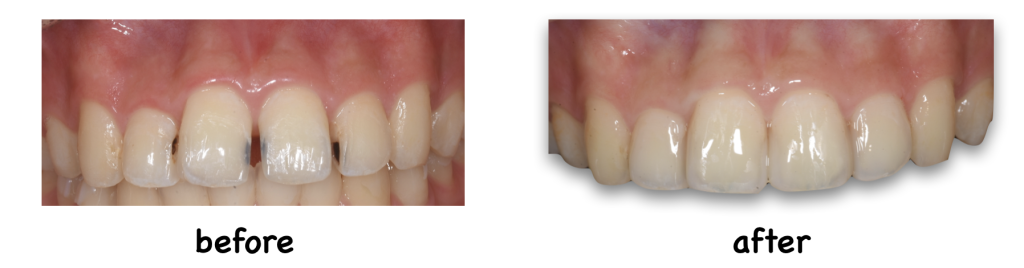

こんにちは! なかむら歯科、院長の中村弘幸です! 本日も症例を紹介させていただきます! こちらの患者様は、すきっ歯を主訴に来院されました。すきっ歯からむし歯にもなってしまっています。 むし歯治療と並行